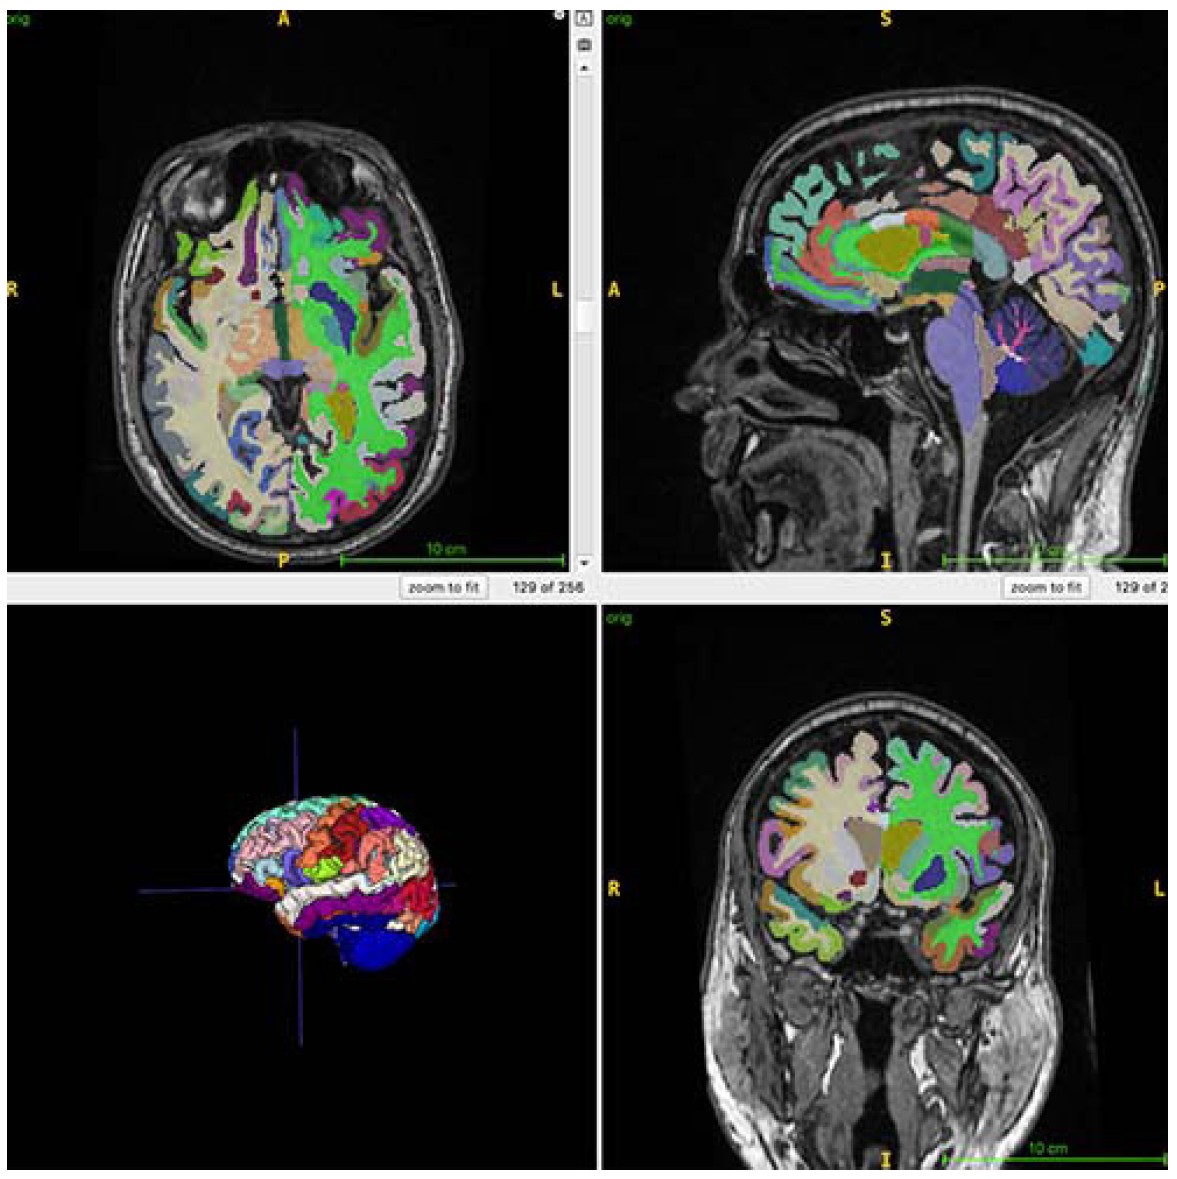

Brain age is the computational estimation of chronological age from a structural MRI scan of the brain. Muscle mass, as tracked by body MRI, can be a surrogate marker for various interventions to reduce frailty and improve brain health, and brain age predicted by structural brain images can lend insight to Alzheimer’s disease risk factors, such as muscle loss.

For the ongoing study, 1,164 healthy individuals (52% women) from four sites were examined with whole-body MRI. The mean chronological age of the participants was 55.17 years. The researchers combined MRI imaging with T1-weighted sequences, a technique that produces images where fat appears bright and fluid appears dark. This allows for optimal imaging of muscle, fat and brain tissue. An artificial intelligence (AI) algorithm was used to quantify total normalized muscle volume, visceral fat (hidden belly fat), subcutaneous fat (fat under the skin) and brain age.